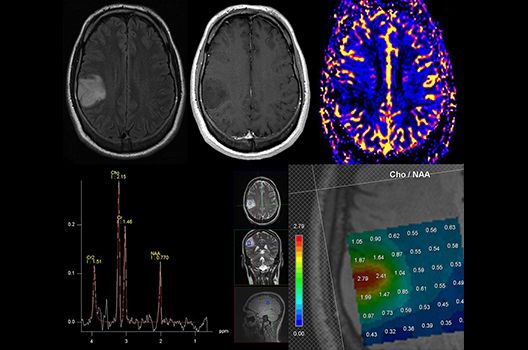

Die Magnetresonanztomographie (MRT) ist ein Verfahren, bei dem durch magnetische Kräfte Bilder des Körperinneren angefertigt werden. In der Neuroradiologie können manchmal kleinste Veränderungen schwere Folgen haben; daher forschen wir an der Entwicklung hochauflösender MRT-Sequenzen, mit denen diese Prozesse und auch einzelne Nervenfaserbahnen sichtbar gemacht werden können. Darüber hinaus sind bei vielen Erkrankungen des Gehirns die Blutgefäße betroffen. Daher arbeiten wir an der Neu- und Weiterentwicklung von MRT-Sequenzen zur Darstellung der Blutgefäße und zur Blutflussanalyse (sog. „Angio-MRT“). Einen besonderen Forschungsschwerpunkt unserer Klinik stellen die MR-Protonenspektroskopie und die funktionelle MRT dar, mit denen die Analyse einzelner chemischer Substanzen im Hirngewebe oder die Darstellung ausgewählter Hirnfunktionen möglich ist.